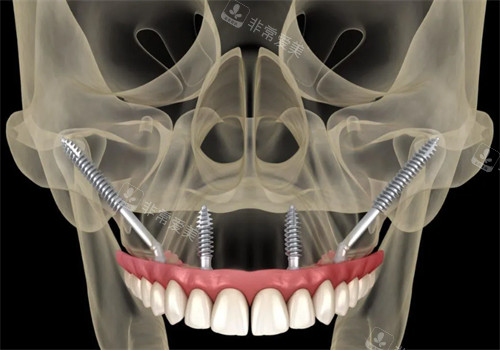

森朗口腔特别擅长穿颧穿翼种植技术,这是针对骨量重的不足患者的解决方案。

传统种植需要先植骨,等待6个月才能种植,而穿颧穿翼技术可以直接植入,大大缩短治疗周期!

穿颧穿翼技术动画示意图

穿颧穿翼种植正面图